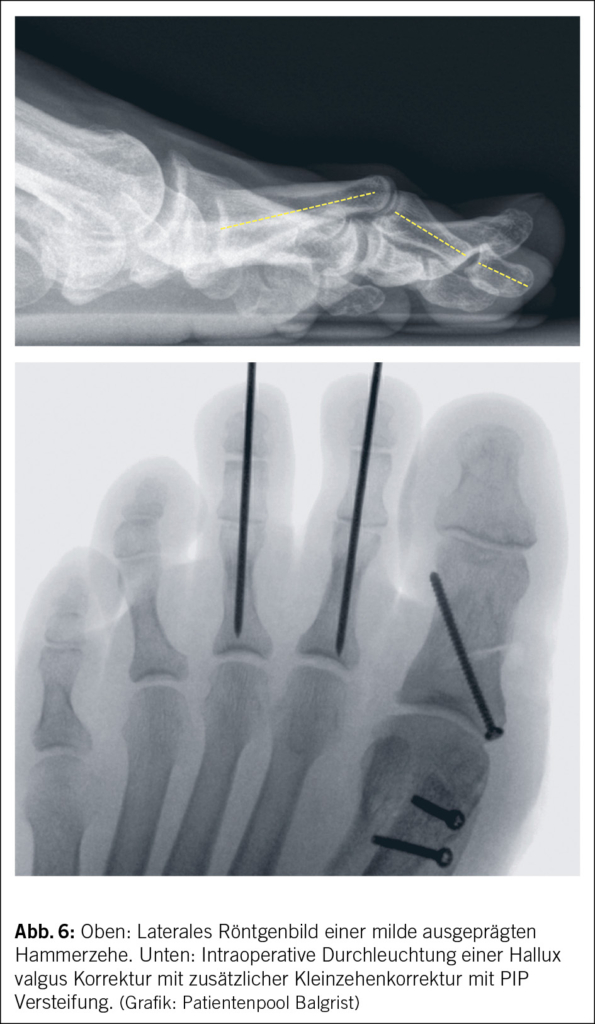

Ebenfalls ist ein Röntgenbild des Vorfusses wichtig, um ossäre Läsionen auszuschliessen.

Alternativ kommt bei starken Fehlstellungen oder auch zeitgleicher Stabilisation im MTP Gelenk die Hohmann-Prozedur infrage. Hierbei wird das proximale interphalangeale Gelenk entfernt und ein Stabilisationsdraht wird eingebracht und für 6 Wochen belassen (Abb. 6) (37). Die Patientenzufriedenheit ist bei korrekter Indikation mit >80 % sehr hoch und hat die Rezidivdeformität als Hauptkomplikation. Daneben sind die am Häufigsten berichteten Unzufriedenheiten Schwellung, Steifigkeit, Taubheit und schlechtere Funktion (37).